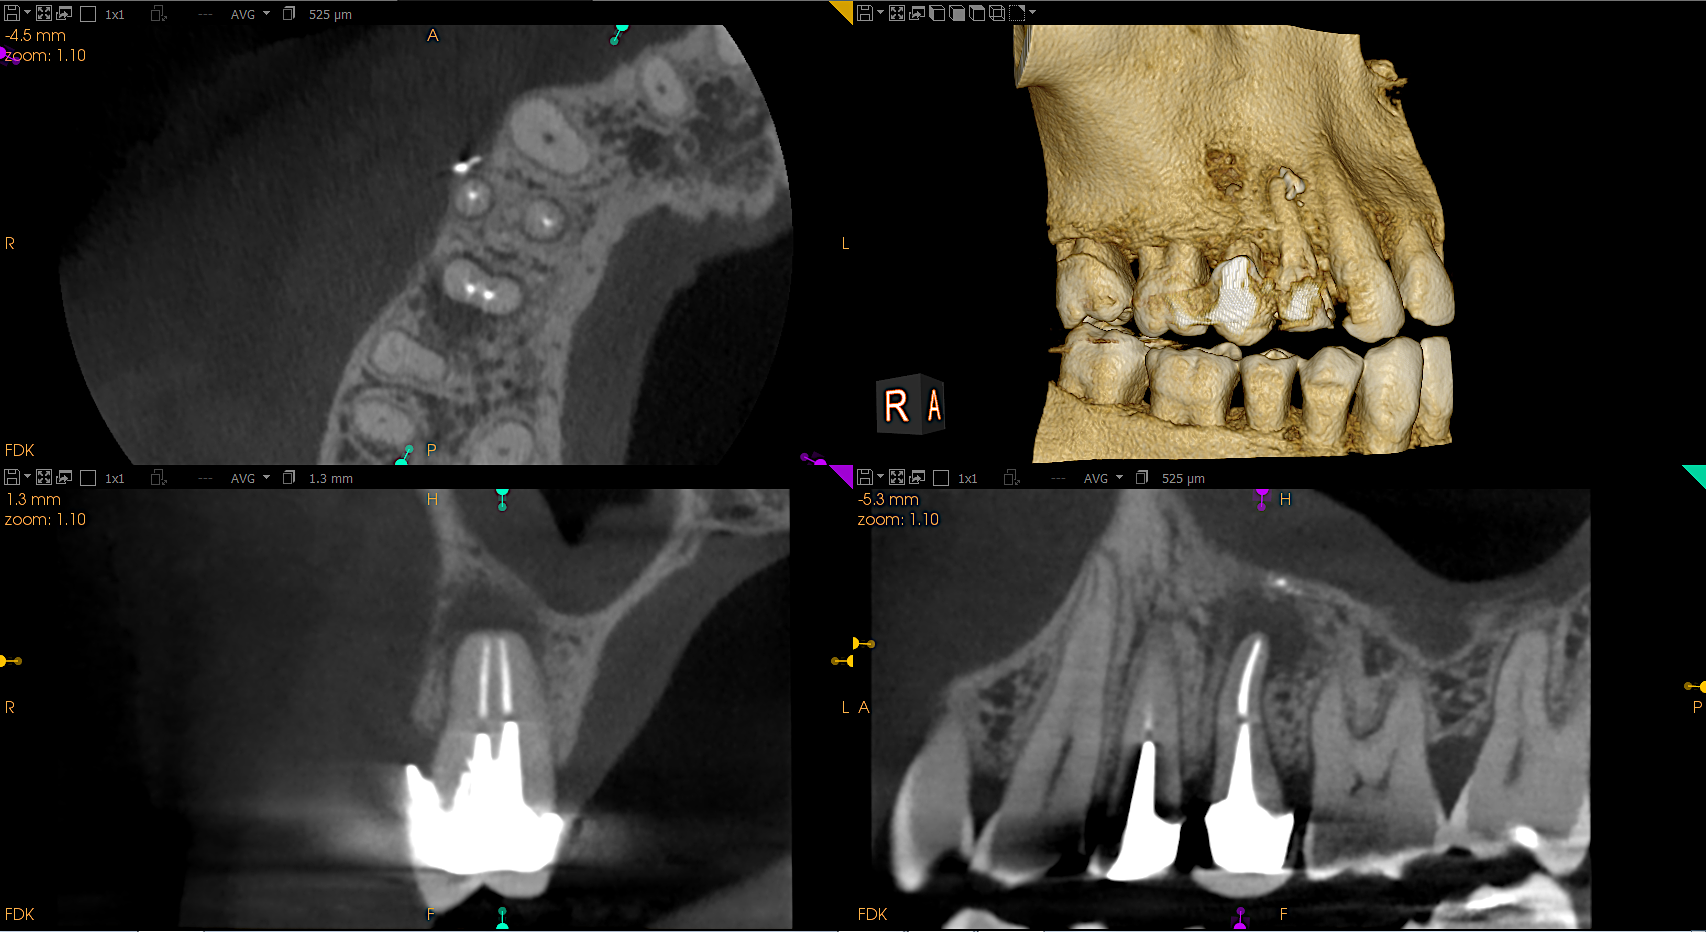

Chirurgia stomatologiczna

Chirurgia szczękowa